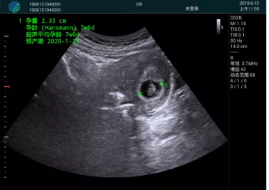

病例一:

清晰顯示孕囊,通過軟件包計算孕齡7w+6d

M20實時引導(dǎo),術(shù)中清晰顯示孕囊被破壞和抽吸針的過程,清晰顯示吸引針

抽吸結(jié)束后縱切子宮,孕囊已被完全抽吸,未見明顯殘留

橫切子宮,發(fā)現(xiàn)右側(cè)宮腔靠近宮角處有少許脫模樣殘留

M20引導(dǎo)下,抽吸針找到右側(cè)宮角處再次清掃

二次抽吸后再次進行超聲檢查,宮腔未見殘留,宮腔線清晰顯示

超聲引導(dǎo)下可視化人流是技術(shù)安全性的保障,一般對人流術(shù)設(shè)備預(yù)算不高,M20具備婦產(chǎn)科軟件包,且穿透力圖像質(zhì)量好,既滿足人流引導(dǎo)需要,也可用于床旁超聲的需求。